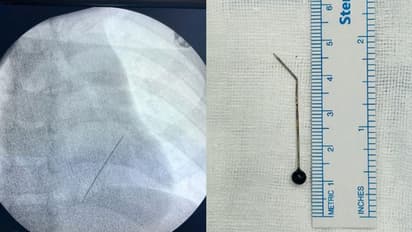

കൊച്ചി: കളിക്കുന്നതിനിടെ അബദ്ധത്തിൽ വിഴുങ്ങിയ സൂചി 7 വയസ്സുകാരന്റെ ശ്വാസകോശത്തിൽ നിന്ന് പുറത്തെടുത്തു. മാലിദ്വീപ് സ്വദേശിയായ കുട്ടി ഈ മാസം 22 നാണ് വസ്ത്രങ്ങളിൽ ഉപയോഗിക്കുന്ന വലിയ സൂചിയായ ഹിജാബ് പിൻ കളിക്കുന്നതിനിടെ അബദ്ധത്തിൽ വിഴുങ്ങിയത്. ഇതേ തുടർന്ന് രക്തസ്രാവം അനുഭവപ്പെട്ട കുട്ടിയെ ഉടൻ തന്നെ മാലിദ്വീപിലുള്ള ഇന്ദിരാഗാന്ധി മെമ്മോറിയൽ ഹോസ്പിറ്റലിൽ എത്തിച്ചു. ഇവിടെ നടന്ന എക്സ്റേ പരിശോധനയിലാണ് സൂചി അപകടകരമായ നിലയിൽ ഇടതുവശത്തെ ശ്വാസകോശത്തിന്റെ ഏറ്റവും അടിത്തട്ടിൽ ലോവർ ലോബിനോട് ചേർന്ന് തിരശ്ചീനമായി കിടക്കുന്നതായി കണ്ടെത്തിയത്.

കടുത്ത ചുമയും രക്തസ്രാവവും തുടരുന്നതിനിടെ കുട്ടിയെ വിദഗ്ധ ചികിത്സയ്ക്കായി അടിയന്തരമായി ഹെലികോപ്റ്ററിൽ മാലിദ്വീപിൽ നിന്ന് കൊച്ചിയിലേക്കെത്തിക്കുകയായിരുന്നു. കൊച്ചി അമൃത ആശുപത്രിയിൽ ചീഫ് ഇന്റർവെൻഷണൽ പൾമണോളജിസ്റ്റ് ഡോ.ടിങ്കു ജോസഫിന്റെ നേതൃത്വത്തിലാണ് കുട്ടിയുടെ ശ്വാസകോശത്തിൽ കുടുങ്ങിയ 5 സെന്റിമീറ്ററോളം നീളമുള്ള സൂചി റിജിഡ് ബ്രോങ്കോസ്കോപിയിലൂടെ പുറത്തെടുത്തത്. മൂന്നരമണിക്കൂറോളം നീണ്ട റിജിഡ് ബ്രോങ്കോസ്കോപ്പി നടപടിക്രമത്തിലൂടെയാണ് ഒടുവിൽ സൂചി പുറത്തെടുത്തത്. മറ്റ് അപകടസാധ്യതകൾ ഒഴിവാക്കാൻ സൂചിയുടെ അഗ്രഭാഗം ശ്വാസകോശത്തിനുള്ളിൽ വച്ച് തന്നെ ചെറുതായി വളച്ച ശേഷമാണ് സൂചി പുറത്തെടുത്തത്.

ഹൃദയത്തിലേക്കുള്ള പ്രധാന രക്തക്കുഴലുകൾക്ക് തൊട്ടടുത്തായാണ് സൂചി കുടുങ്ങിക്കിടന്നിരുന്നത് എന്നത് വലിയ വെല്ലുവിളിയായിരുന്നെന്നും, ഇത്രയും നീളത്തിലുള്ള സൂചി ഓപ്പൺ സർജറി കൂടാതെ, റിജിഡ് ബ്രോങ്കോസ്കോപിയിലൂടെ പുറത്തെടുക്കുന്നത് അപൂർവമാണെന്നും ഡോ.ടിങ്കു ജോസഫ് പ്രതികരിക്കുന്നത്. ആശുപത്രിയിൽ നിന്ന് ഡിസ്ചാർജായ കുട്ടി മാതാപിതാക്കൾക്കൊപ്പം ഞായറാഴ്ച മാലിദ്വീപിലേക്ക് മടങ്ങും.